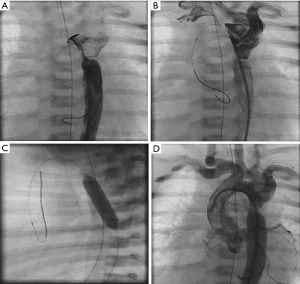

In case of a restrictive atrial septum in HLHS, atrial decompression tends to be more complicated due to an associated small left atrial dimension, atypically positioned PFO or even complete closed atrial septum; requiring fluoroscopic guidance by an experienced interventionalist (24). The challenging cross of the PFO or small restrictive ASD needs oftentimes a special technique, as by utilizing a 2.5 curved right Judkins (4 Fr) together with a floppy 0.014 inch coronary wire; once the wire is crossed and curved in the LA or directed to one of the pulmonary veins, the Judkins-catheter is than advanced over the floppy-wire exchanging the floppy to a stiff coronary guide wire to perform a Rashkind procedure or gradual static balloon dilatation of the atrial septum. Sometimes the balloon technique including the use of cutting balloons remains insufficient; in these cases stent implantation is required. In our institution, we use nowadays self-expandable stents (Sinus SuperFlex DS; 8×15 or 9×15 or 18 mm) instead of balloon expandable stents. The open-cell design of self-expandable stents reduces the risk of stent embolization, and if it should occur, the stent design facilitates percutaneous retrieval (Figure 1). In case of a closed atrial septum, perforation of the septum is performed by Brockenbrough trans-septal needle technique or by radio-frequency technique.

Cases of prostaglandin-refractory duct stenosis, as seen in newborns admitted with cardiogenic shock and metabolic acidosis, should be immediately transferred to the catheter laboratory for stent implantation; immediate duct stenting is the most effective and quickest therapy (24,25). Requiring however, a well-prepared cardiac team and a sufficiently equipped catheter stock (Figure 2A,B,C,D,E,F).